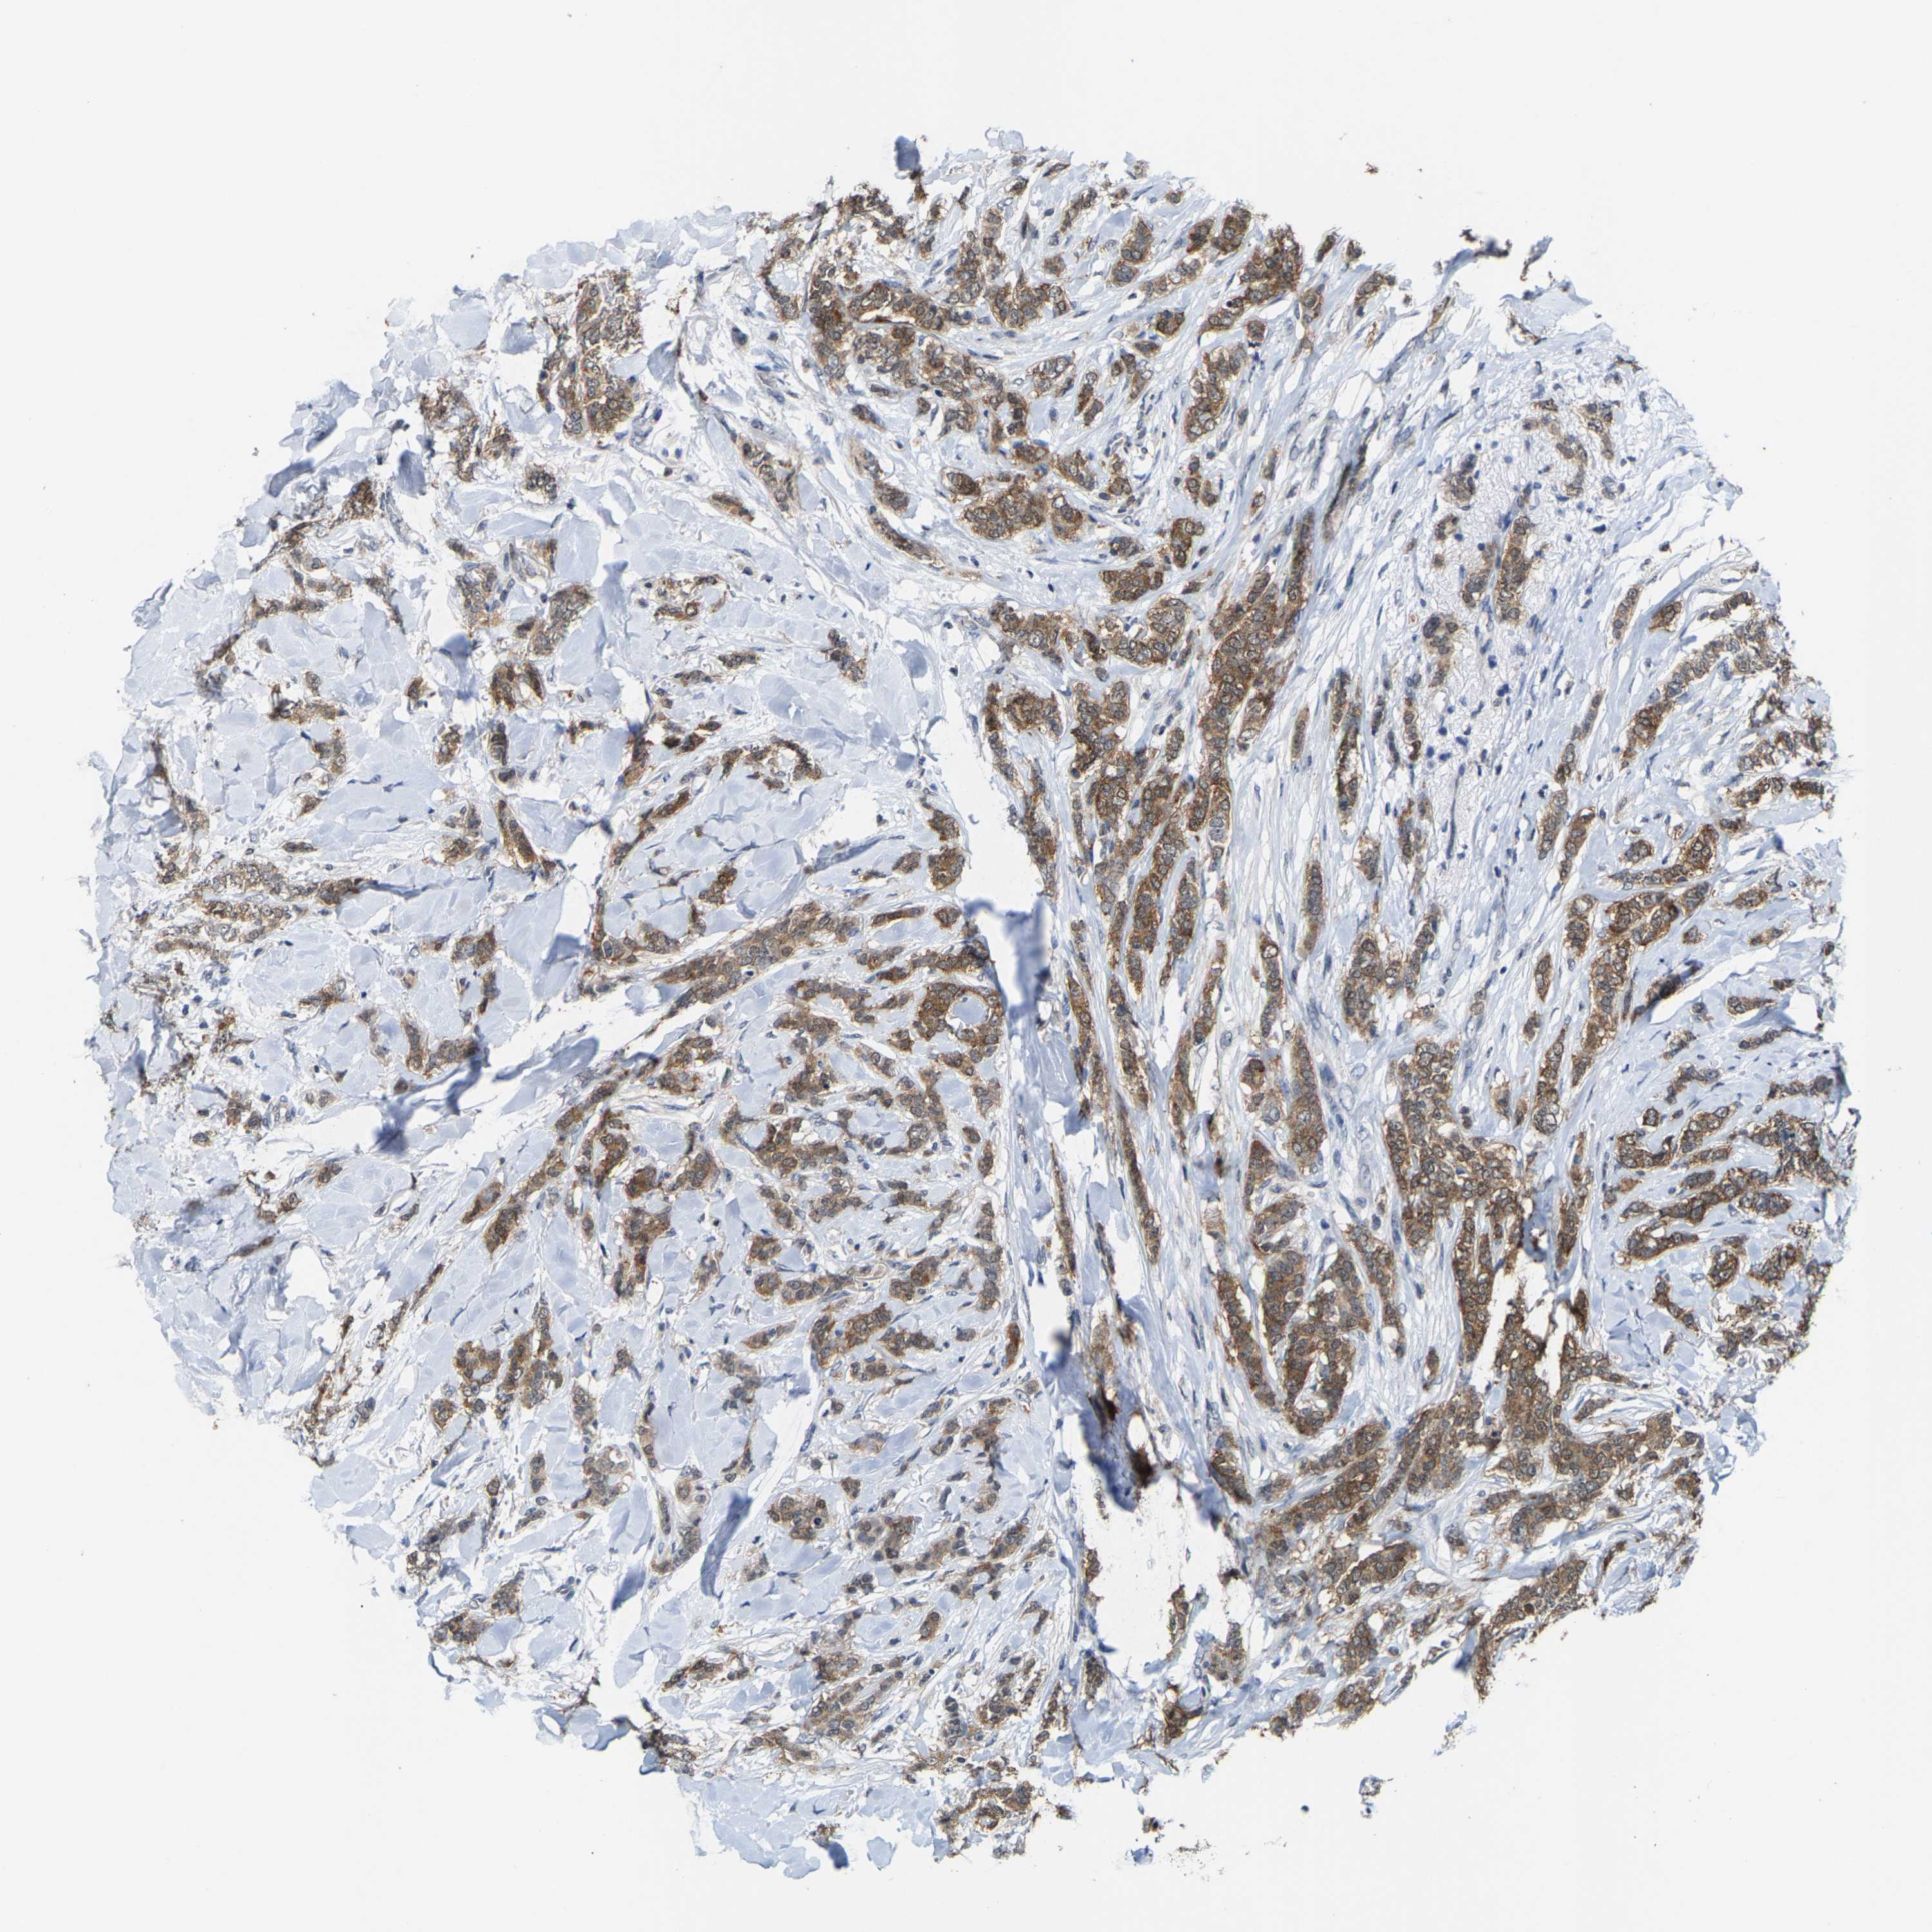

CANCER BREAST CANCER Show tissue menu

BRCA TCGA BRCA VALIDATION PROTEIN EXPRESSION